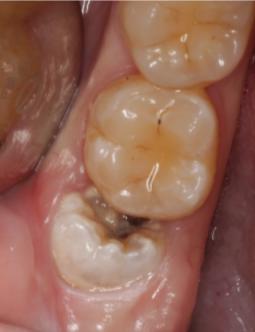

前倾阻生智齿,它的牙冠向前倾倒,直抵邻牙颈部,无论在口腔内还是X线片上都很直观,在形态上,跟警察跪压在黑人颈部非常相似,而且造成的后果也基本相同。

前倾智齿与邻牙形成一个敞开的间隙,经常会残留食物残渣,并且属于刷牙难以清理的死角,因此在邻牙邻面极易沉积菌斑,时间稍长即可形成邻面龋,龋损一旦攻破薄弱的牙骨质进入牙本质,邻牙即进入快速崩解毁灭期,于是产生临床上常见的“拔一送一”现象。

智齿顶坏了邻牙,一般都是因为疼痛剧烈而就诊,不是智齿痛而是邻牙痛,一般需要X线片进行确诊。临床根据邻牙龋损的深度,多半都是进行根管治疗或者拔除邻牙,但智齿本身大多是不治也不拔的,说实话,它真的像美国警察。